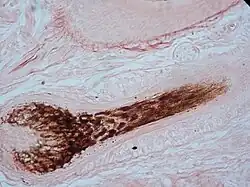

El folículo piloso es la parte de la piel que da crecimiento al cabello al concentrar células madre, formándose a partir de una invaginación tubular. Cada cabello descansa sobre un folículo piloso, siendo este, la estructura cutánea más dinámica y una de las más activas de todo el organismo.

En la base del cabello, una fina red de vasos sanguíneos forma la raíz del mismo, alrededor de la cual hay una estructura blanca llamada bulbo, que es la región proliferativa. El bulbo se compone de dos o tres capas de células basales precursoras de los elementos celulares que emigrarán a la superficie por el interior de la vaina externa. En la parte inferior se hallan las células germinativas que se diferencian en anillos concéntricos celulares. Los tres anillos externos producirán las capas de la vaina pilosa interna y los tres anillos internos darán lugar al futuro cabello.

En la base del folículo hay una estructura pequeña con forma de cono llamada papila que es donde tienen origen las células que forman parte del cabello. La papila dérmica está formada por las células fibroblásticas y es la responsable del control del ciclo piloso.